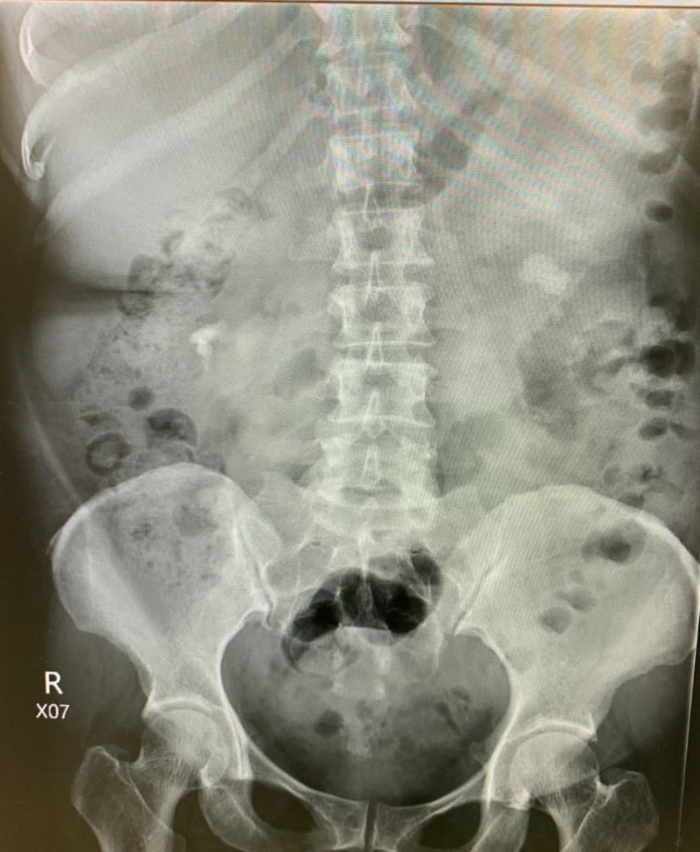

วันนี้ผมต้องผ่าตัดนิ่วเขากวางขนาดใหญ่ แต่ปัญหาคือเครื่องมือที่ใช้สลายนิ่วเป็นประจำเสีย ซ่อมไม่ได้ด้วย ต้องซื้อใหม่สถานเดียว จะใช้เครื่องมือกระแทกนิ่วตัวอื่นก็หวั่น ๆ

สุดท้ายแก้ปัญหาด้วยการยืมเครื่องมือสลายนิ่วมาใช้ 2 สัปดาห์ สอบถามผู้แทนเครื่องมือถึงราคา สนนราคา 2 ล้านกว่าบาท โรงพยาบาลก็ไม่ค่อยมีเงินจึงไม่รู้ว่าเมื่อไหร่จะมีใช้